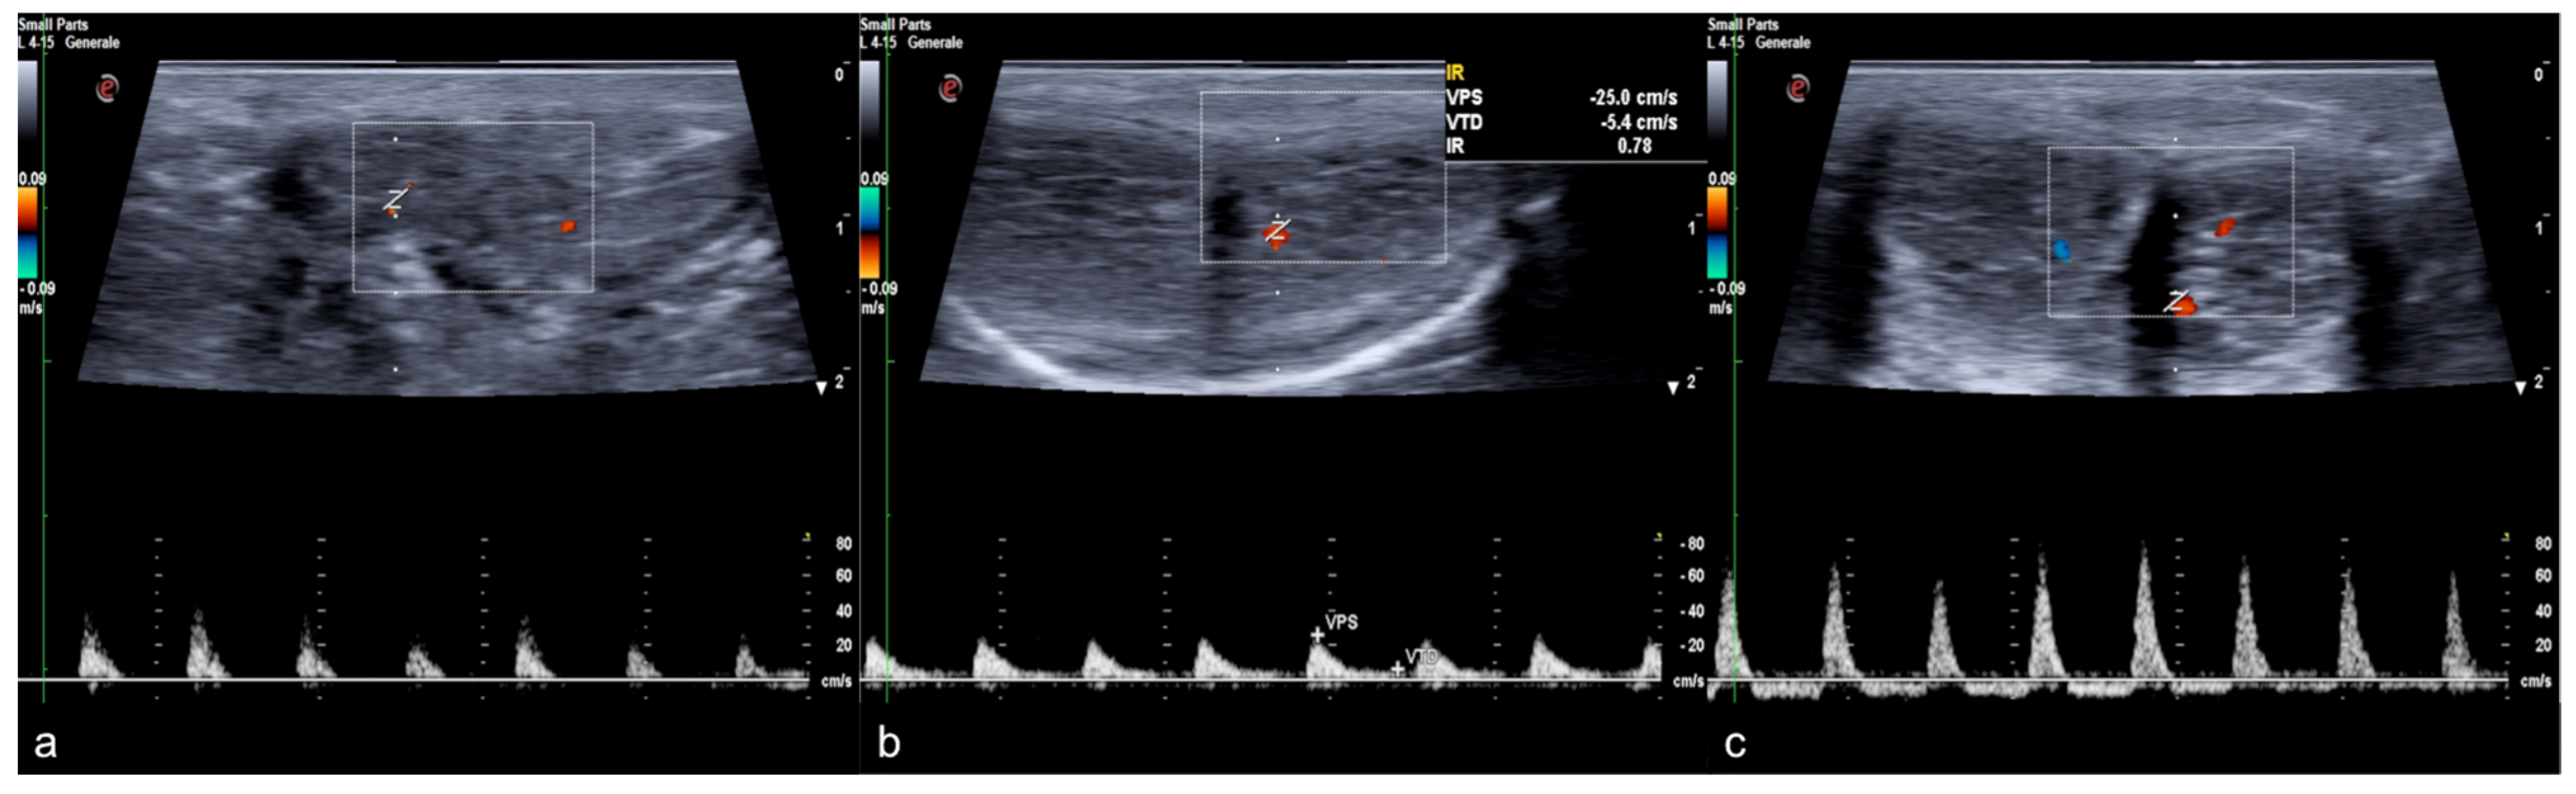

Figure 9.

Cav-MRI. The GRE T1W 3D FS axial images displayed with MIP reconstruction after 1 min (a) and 5 min (b) from the intracavernosal injection of the contrast agent show an ineffective penis erection sustained by venous leakage mediated by the deep dorsal vein of the penis ((a), arrowhead) that feeds the obturator veins ((b), arrows). The 3D Volume-Rendering (c) reconstructed 1 min after the administration of the contrast agent documents the rapid penis detumescence with a dominant deep dorsal venous collector (arrow).

B-mode ultrasound and pulsed Doppler performed before and after drug-induced erection are the most widely used methods before resorting to invasive instrumental investigations. As is well known, the speed and morphology of the flow-metric curve detected at pulsed Doppler varies at different times during the erective process, in close dependence to the endocavernosal pressure, therefore observing physiologically high resistance flow spectra with inversion of the diastolic component during complete erection (Figure 10).

Figure 10.

Color and pulse Doppler penile Ultrasound performed in different phases of erection. During the flaccid state (a), the waveform shows a monophasic pattern with minimal diastolic flow; during the tumescence (b), the waveform shows a progressive decrease in diastolic flow; during the full erection (c), the waveform shows a diastolic flow reversal.

Otherwise, in the presence of increased venous outflow, a persistently high diastolic velocity is observed even at maximum erection obtained by drug induction: when the diastolic velocity is greater than 10 cm/s, venous etiology of ED should be suspected. An imaging contrastographic study for evaluation of the venous circulation must be carried out to confirm the diagnosis of ED by venous outflow (Figure 2) [18,25,26].